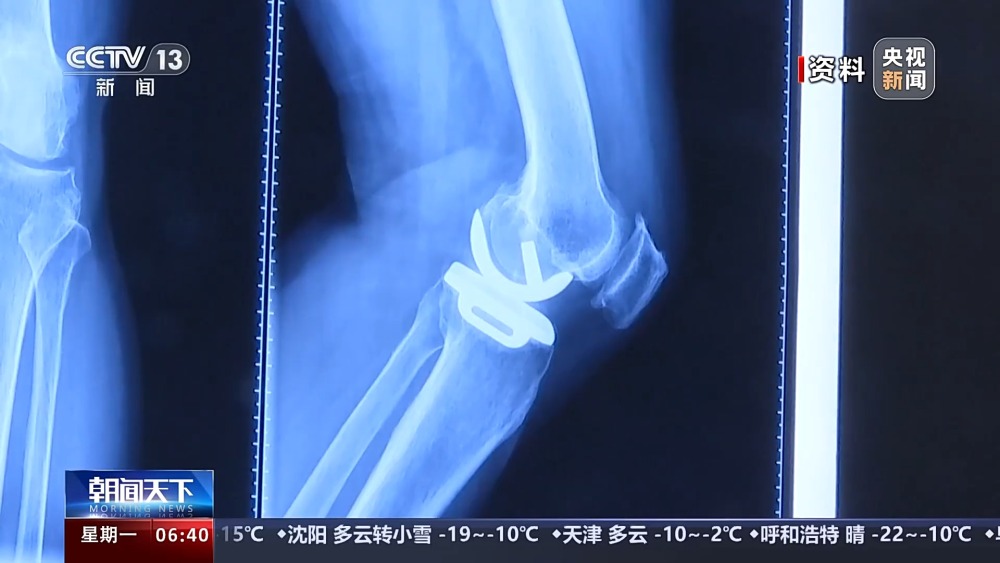

目前,我國(guó)有超過1億人患有骨關(guān)節(jié)炎,65歲以上人群中,骨關(guān)節(jié)炎發(fā)病率接近50%。以前,嚴(yán)重骨關(guān)節(jié)炎患者主要通過膝關(guān)節(jié)置換手術(shù)來(lái)維持行走等基本功能。膝關(guān)節(jié)置換手術(shù)存在術(shù)后關(guān)節(jié)僵硬、長(zhǎng)期疼痛等問題。保膝治療包括藥物、理療等保守治療,以及手術(shù)治療。

保膝手術(shù)主要包括截骨術(shù)和單髁置換術(shù),其中截骨術(shù)在解決患者疼痛癥狀的同時(shí),阻止下肢異常應(yīng)力對(duì)膝關(guān)節(jié)的進(jìn)一步損傷,膝關(guān)節(jié)內(nèi)所有軟骨韌帶、半月板都得到了保留。內(nèi)側(cè)單髁置換術(shù),使膝關(guān)節(jié)外側(cè)健康的軟骨和半月板得到了保留,膝關(guān)節(jié)內(nèi)外側(cè)的韌帶維持原有狀態(tài),患者康復(fù)后,擁有正常的膝關(guān)節(jié)功能。